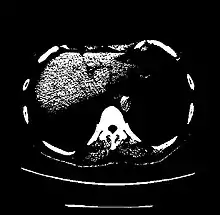

| Liver | 60 ± 6[23] | |